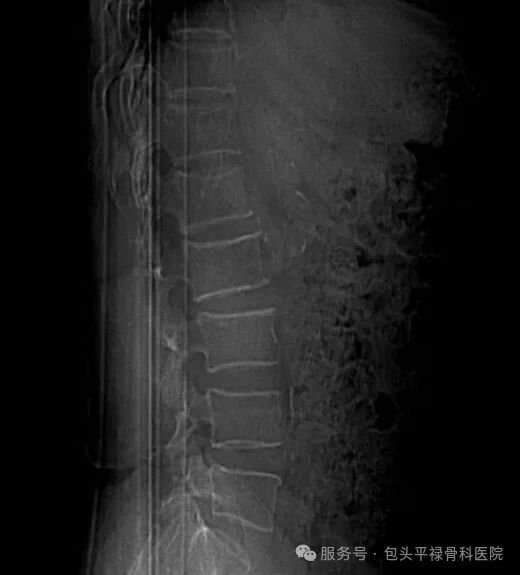

骨质疏松示意图-图片来源于网络,侵删

骨质疏松症是一种代谢性骨病,主要表现为骨量减少、骨组织微结构破坏和骨脆性增加,骨折风险显著增高。患者早期通常没有明显症状,往往骨折后才发现,因此被称为“沉默的骨骼杀手”。